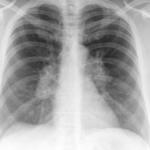

Sarcoid

Album: Sarcoid